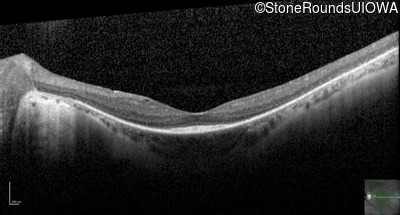

Optical Coherence Tomography - Right - 20/30 +2

Exemplar / OCT Stack